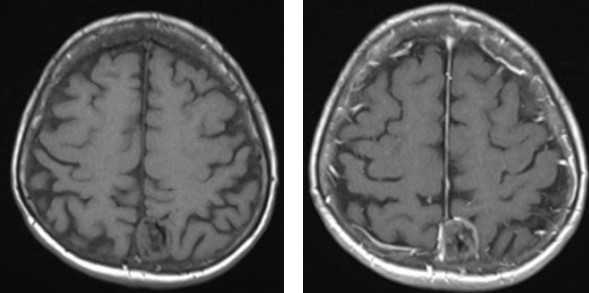

Без внутривенного контрастирования С внутривенным контрастированием

Проведение МРТ головного мозга с контрастом

Контрастное исследование предпочтительно при подозрении на опухоли или уже установленном диагнозе, если больного проверяли раньше другими методами. Контраст, введенный в кровь, попадает в мозг и делает более заметными патологические очаги на фоне здоровых тканей. По скорости и характеру накопления контрастного вещества, границам очага врач может отличить доброкачественную опухоль от злокачественной.